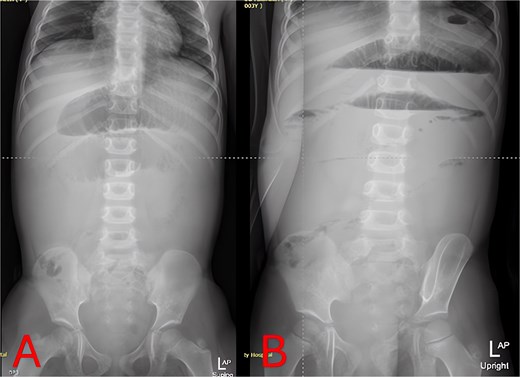

Plain abdominal radiographs revealed centrally dilated small-bowel loops with paucity of distal gas (Fig. 1A) and multiple air–fluid levels without free subdiaphragmatic air (Fig. 1B), consistent with mechanical small-bowel obstruction. Initial management, including nasogastric decompression, nil per os (NPO) status, and intravenous ceftriaxone (75 mg/kg once daily) plus vancomycin (15 mg/kg every 6 hours), failed to improve radiographic findings after 24 hours (Fig. 2A and B), prompting further imaging.

Twenty-four-hour follow-up abdominal X-rays. (A) Supine view 24 hours postadmission with persistent small-bowel distension. (B) Upright view 24 hours postadmission confirming ongoing air–fluid levels and no colonic gas.